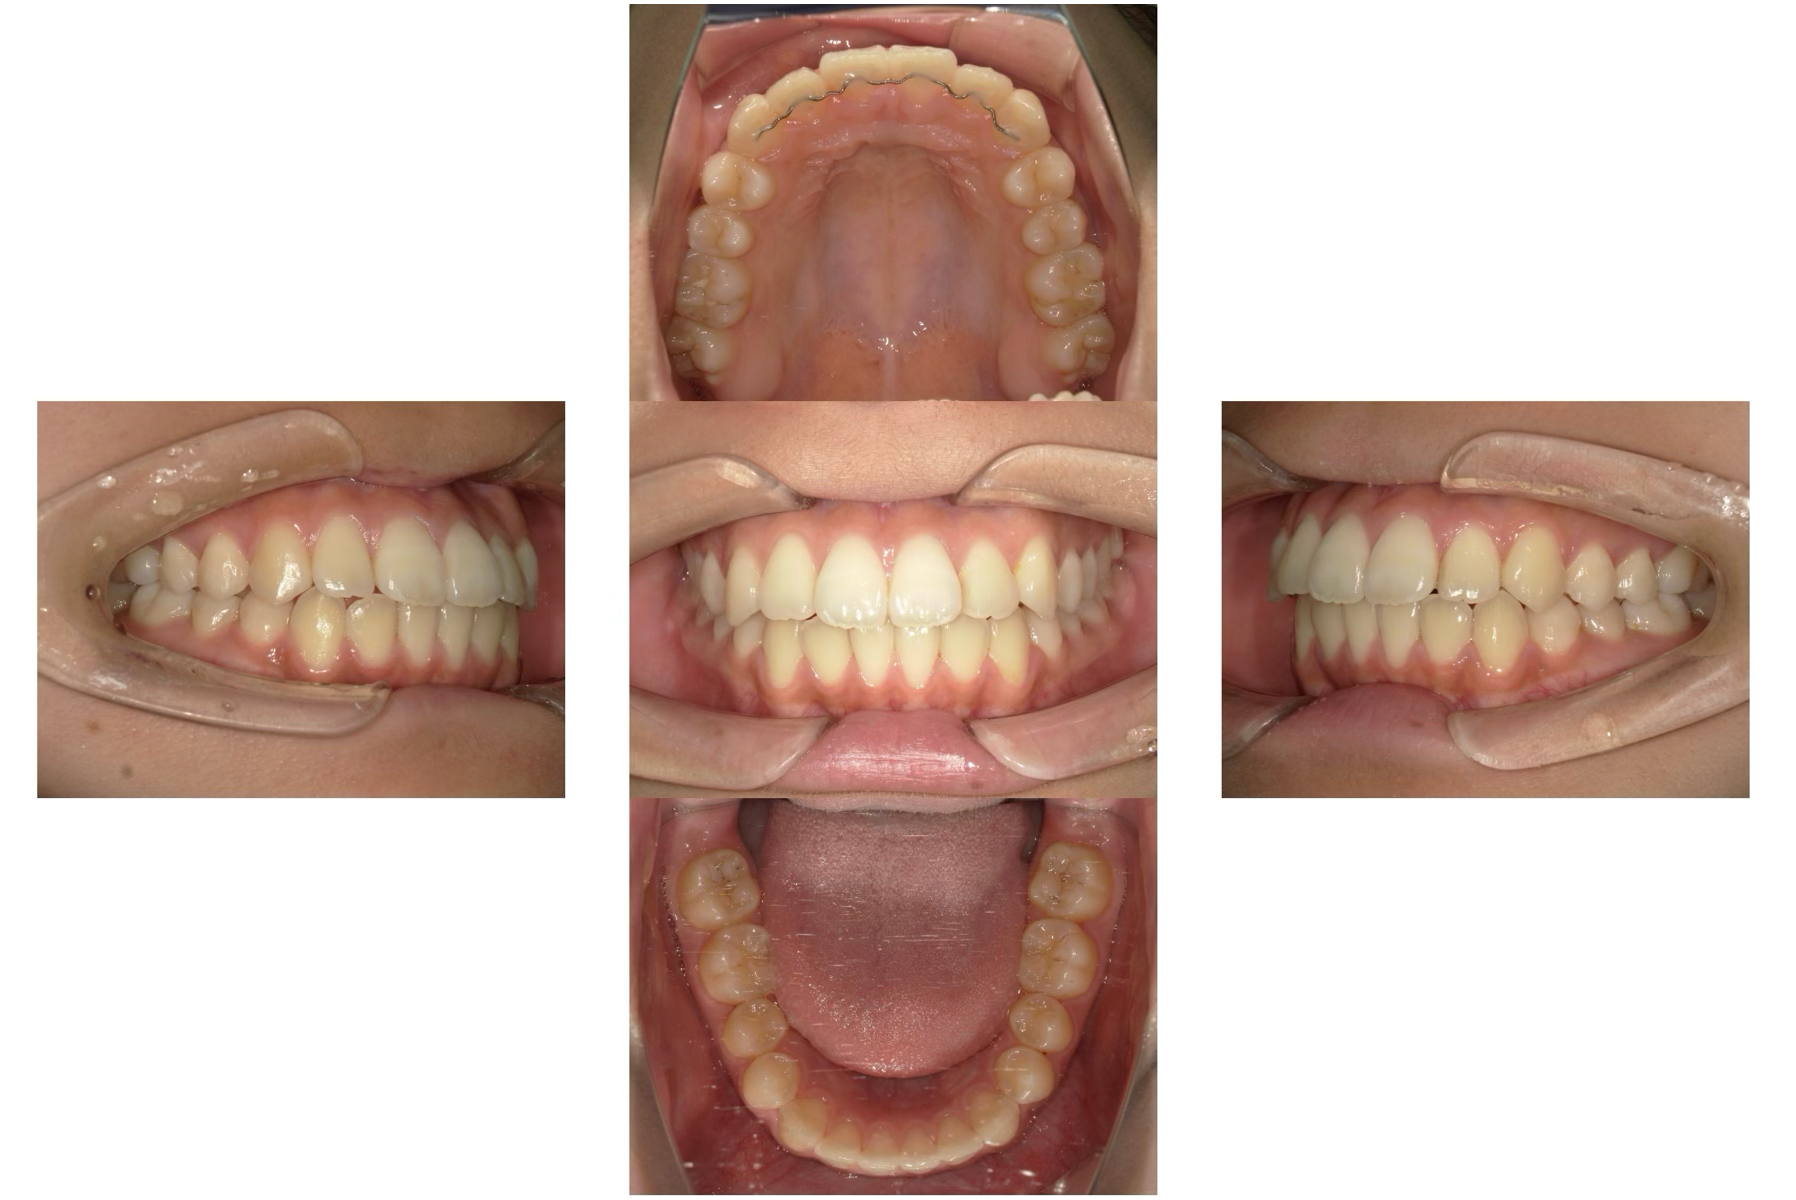

八重歯のマウスピース矯正治療

Before

After

年齢

16歳

主訴

八重歯が気になる。

治療期間

1年

治療費

990,000円(保定装置含む)

概要

八重歯が気になり人前であまり笑顔を見せれない。

唇が閉じにくいこともあり、口の中が乾燥していることがある。

リスク

患者さまの装着時間によって移動量に個人差があります。

マウスピースの入れ始めは痛みを伴うことがあります。

歯の移動を可能にするための隙間を作るために歯を削る必要がある場合があります。

矯正治療中は治療過程で噛み合わせが不安定になり、顎関節症を引き起こす可能性があります。

重度なケースではマウスピース矯正治療が適応とならないケースがあります。

矯正治療後に後戻りを起こすことがあります。

矯正治療が終わり笑顔にも自信を持つことができ、噛み合わせも整ったことで審美的にも機能的にも満足されています。